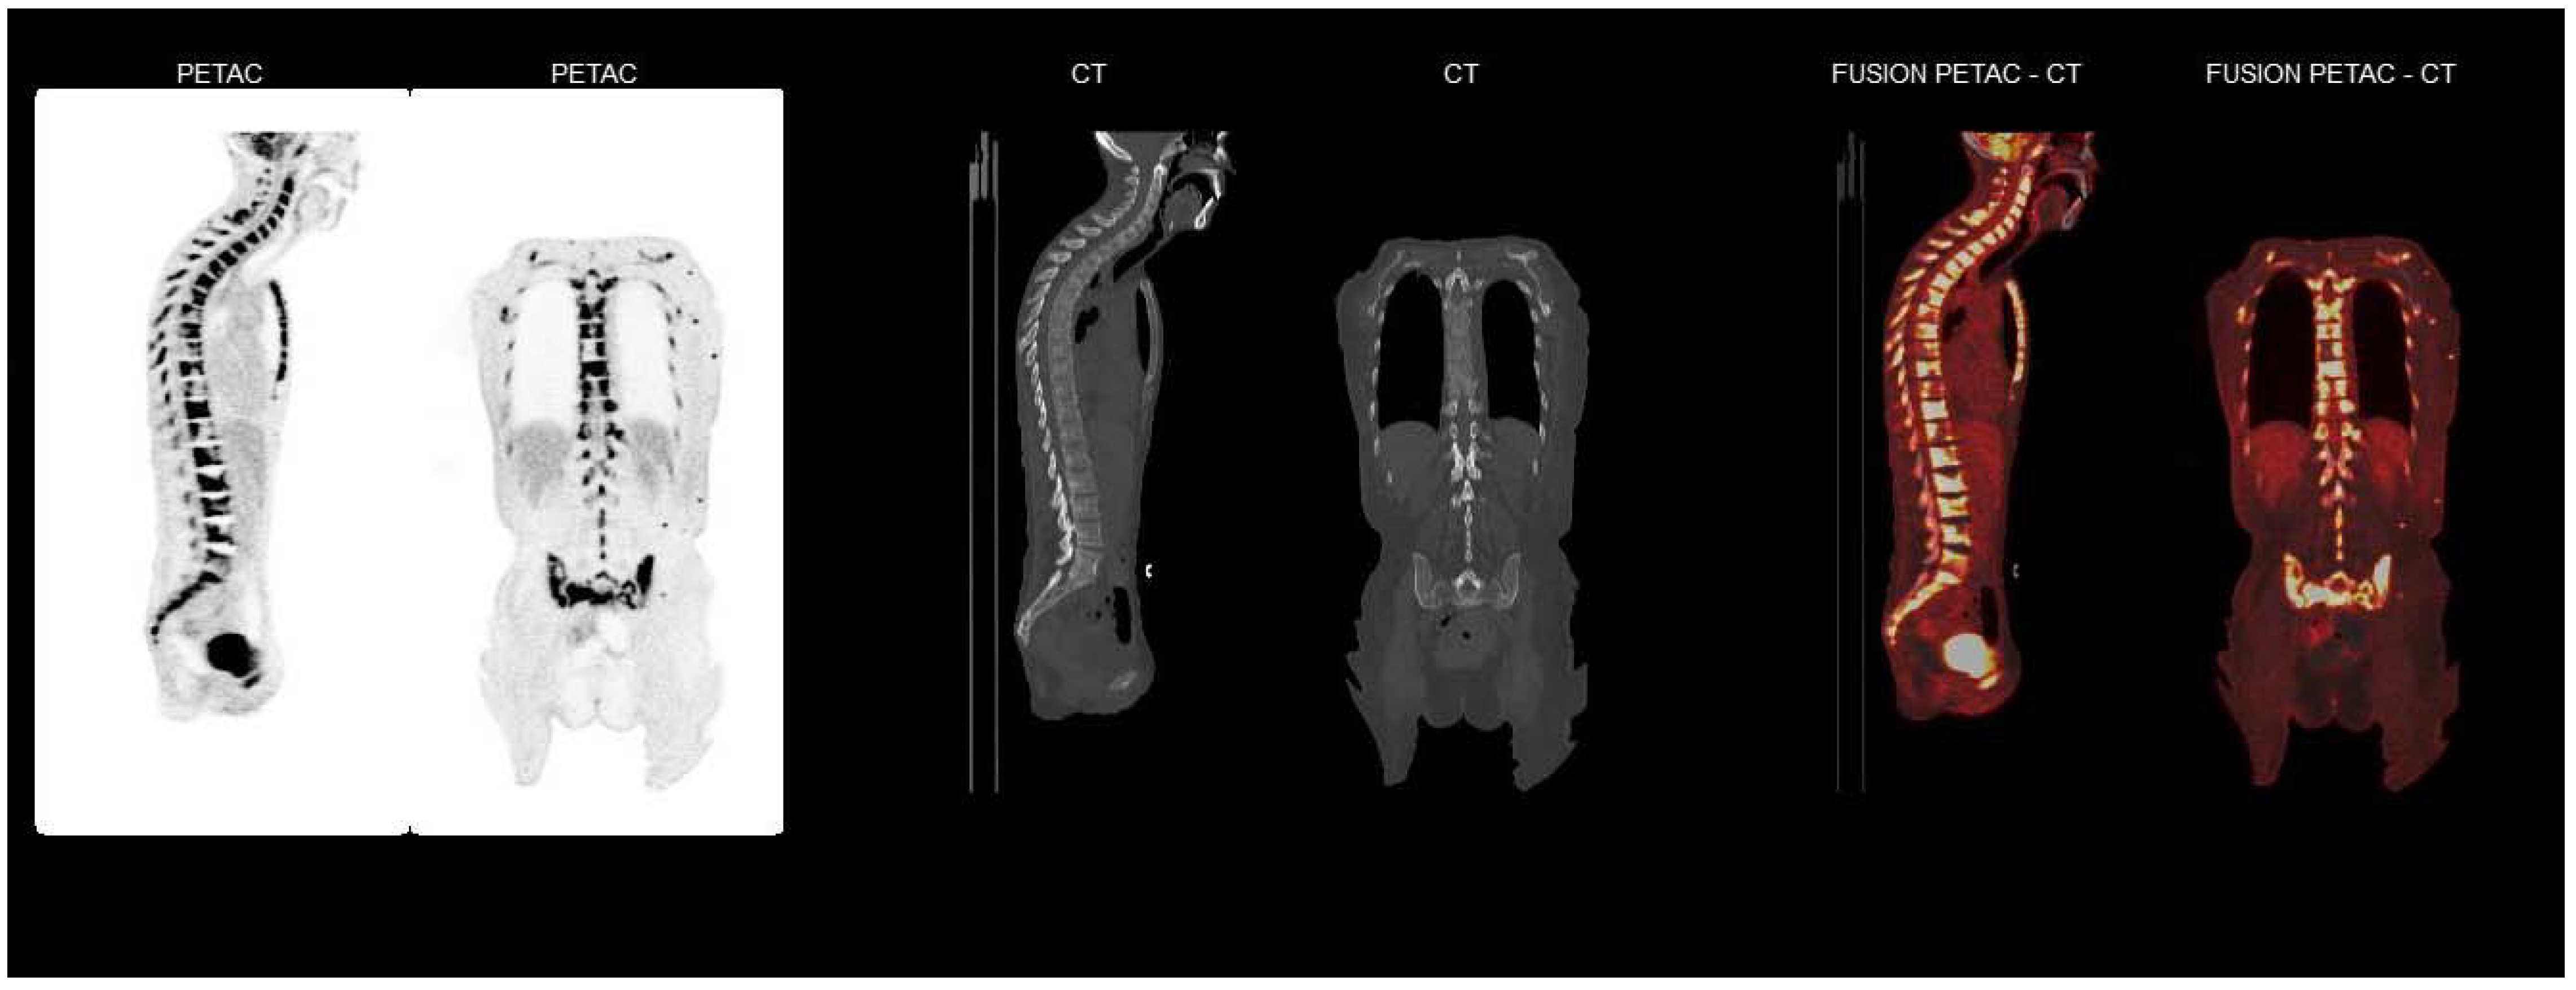

2. Case Report